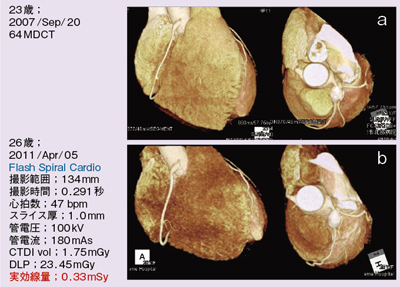

Amazon.com: CT冠動脈造影実践学: 9784498013568: unknown, 冠動脈CTによる狭心症の診断,

冠動脈CTによる狭心症の診断, 沖縄県医師会_沖縄県医師会報(2013年3月号),

沖縄県医師会_沖縄県医師会報(2013年3月号), 放射線 CT - 榊原記念病院,

CT装置|徳島赤十字病院, 320列面検出器CTによる新しい冠動脈CT技術 吉岡邦浩(岩手医科,

320列面検出器CTによる新しい冠動脈CT技術 吉岡邦浩(岩手医科, 桜橋渡辺未来医療病院 MDCT検査予約,